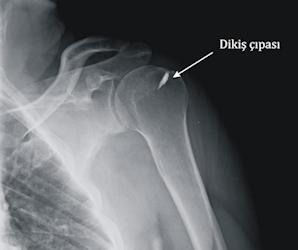

Artroskopik rotator manşet onarımı, ameliyathane şartlarında ve anestezi altında yapılır (Video 2). Omuz çevresinde değişik noktalardan 1cm boyunda küçük kesiler yapılır. Bu kesilerden yerleştirilen kamera sistemleri ile omuz eklemi ve kas yırtığı bölgesi değerlendirilir. Eklem içinde eşlik edebilecek diğer sorunlar düzeltildikten sonra, kas yırtığı tazelenir ve kemikten ayrılmış olduğu bölgeye dikiş çapası adı verilen titanyum implantlar ile tutturulur (Resim 5 ve 6). Hastanede kalış süresi 1 gecedir. Bazı durumlarda artroskopik cerrahiyi sonlandırıp mini-açık cerrahi adı verilen küçük bir kesi ile işleme devam etmek gerekli olabilir.

Resim 6: Dikiş çapası ile rotator manşet onarımı yapılan hastanın ameliyat sonrası röntgen grafisi